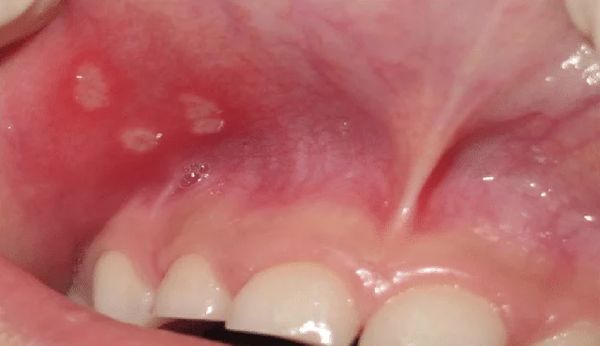

- Афтозный стоматит — отмечается примерно в 87, 5 % случаев [3]. Проявляется болезненными мелкими язвочками на слизистой оболочке полости рта (на щеках, языке и дёснах). При афтозном стоматите, в отличие от герпетического, нет везикулярной стадии, т. е. стадии с пузырьками.

![Язвы во рту при афтозном стоматите [19] Язвы во рту при афтозном стоматите [19]](/media/bolezny/sindrom-marshalla/yazvy-vo-rtu-pri-aftoznom-stomatite-19_s_mTpHbT6.jpeg?dummy=1775198932971)

Язвы во рту при афтозном стоматите [19]